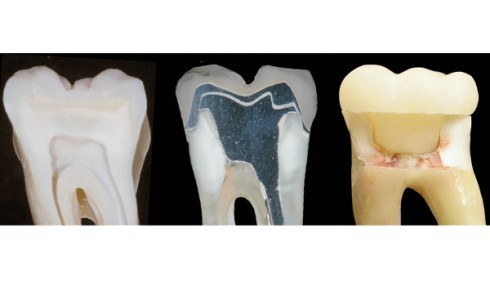

Article réservé à nos abonnés Préparations pour endocouronnes

Vrai ou faux… Question 1. La limite cervicale de l’endocouronne est réalisée sous forme d’un épaulement ou d’un congé large....